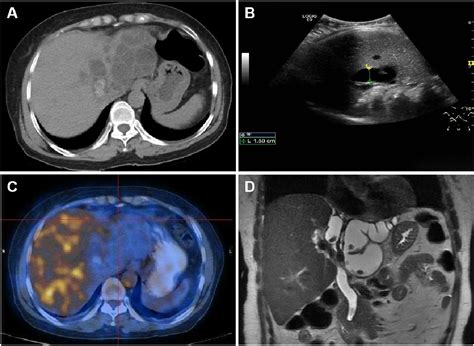

To evaluate the health of the hepatobiliary system, clinicians utilize a combination of blood tests and diagnostic imaging. Laboratory markers, such as alkaline phosphatase, bilirubin, and gamma-glutamyl transferase (GGT), provide a snapshot of how well the liver and biliary ducts are functioning. Imaging technology, however, provides the visual evidence needed to identify structural anomalies.

Abdominal Ultrasound Visualizing stones or tumors Non-invasive and radiation-free

MRCP Detailed duct imaging High-resolution view of bile ducts

HIDA Scan Checking gallbladder function Functional analysis of bile flow